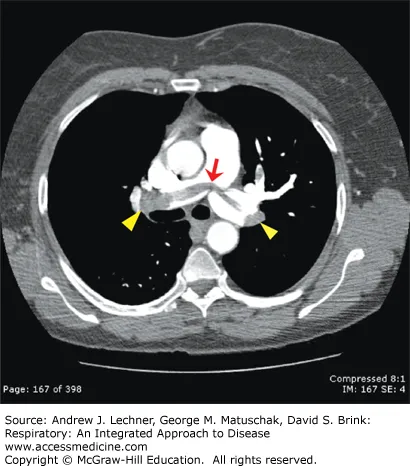

Pulmonary Embolism - Clot on the Move

- Pathophysiology: Obstruction of pulmonary artery, usually from deep vein thrombosis (DVT).

- Risk Factors: Virchow's Triad (stasis, hypercoagulability, endothelial injury) - recent surgery, malignancy, immobility.

- Presentation: Sudden-onset dyspnea, pleuritic chest pain, tachypnea, tachycardia. Massive PE can cause syncope, hypotension.

- Diagnosis: Best initial test is CT Angiogram (CTA). V/Q scan if CTA contraindicated.